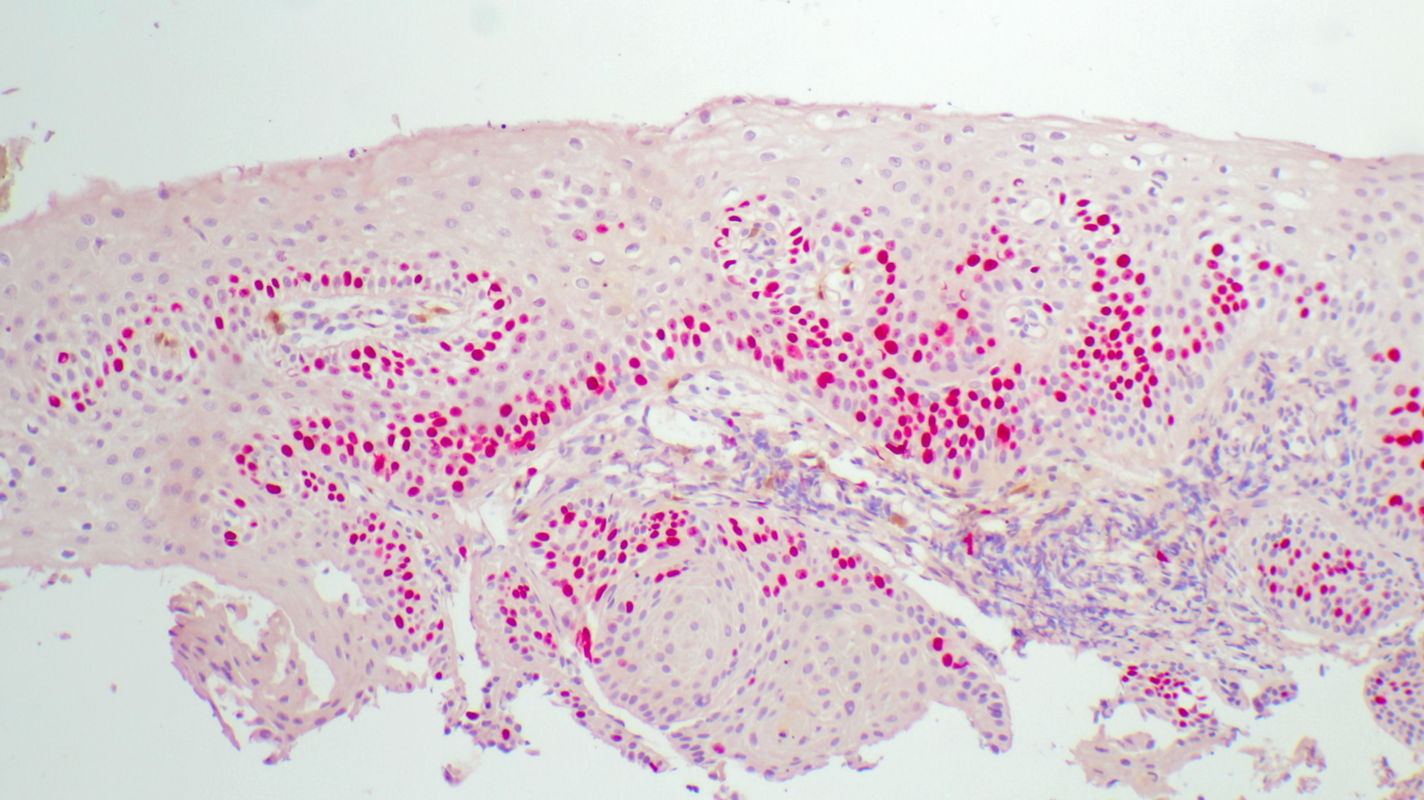

Histopathology of tissue sampled at 11 o’clock by strip biopsy shows normal metaplastic squamous epithelium. The immune marker Ki67 is expressed only in the basal cell layer, and p16 is not detected.

Histopathology findings are interpreted as normal.